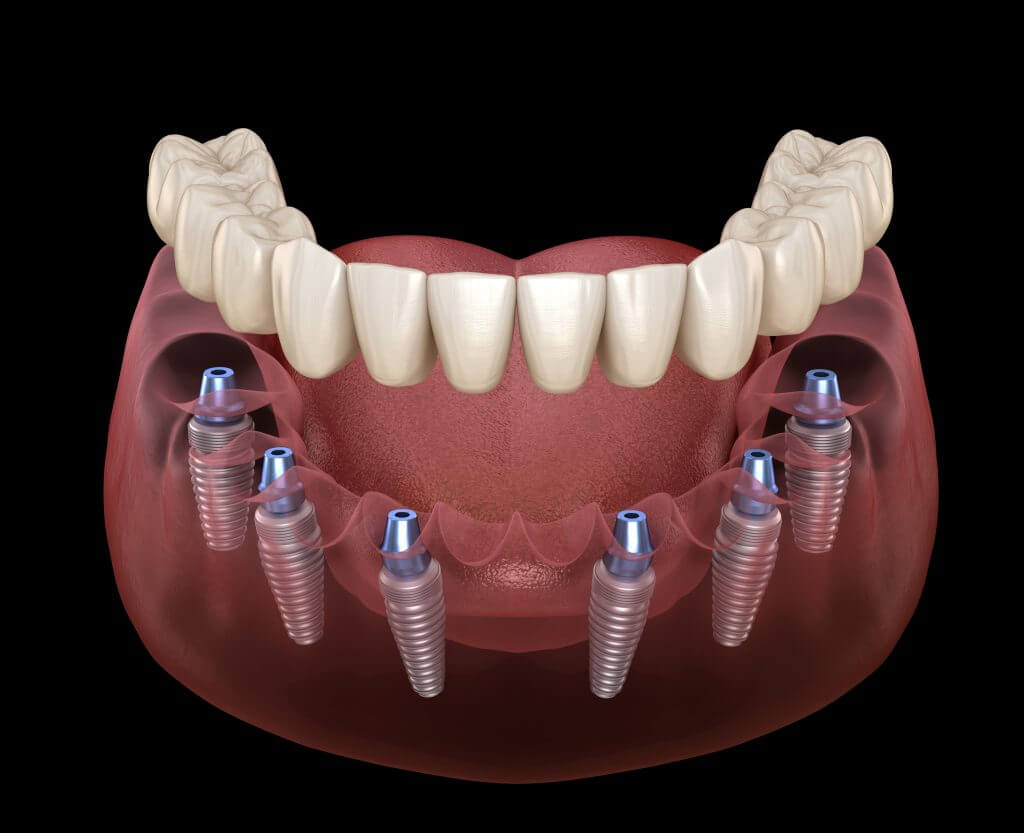

1. Endosteal Implants

The world ‘endosteal’ means ‘inside the bone’. This refers to its integration inside the jawbone, working as a natural root for prosthetic crowns. Endosteal implants are the preferred option for patients having enough jawbone to hold them in place.